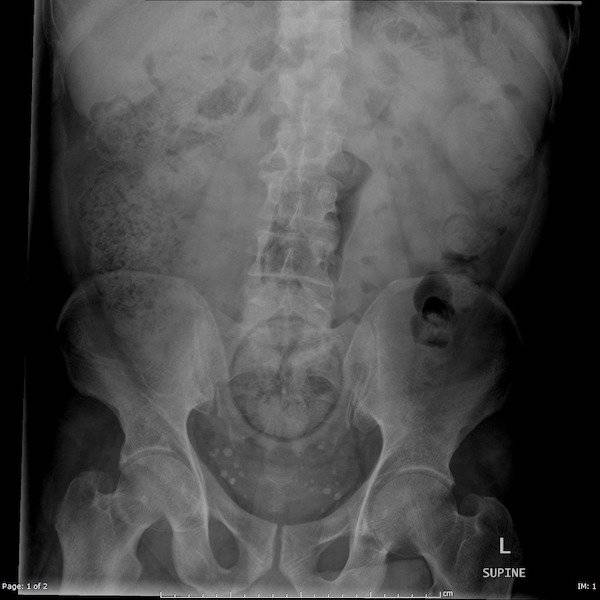

The effects of Gout.